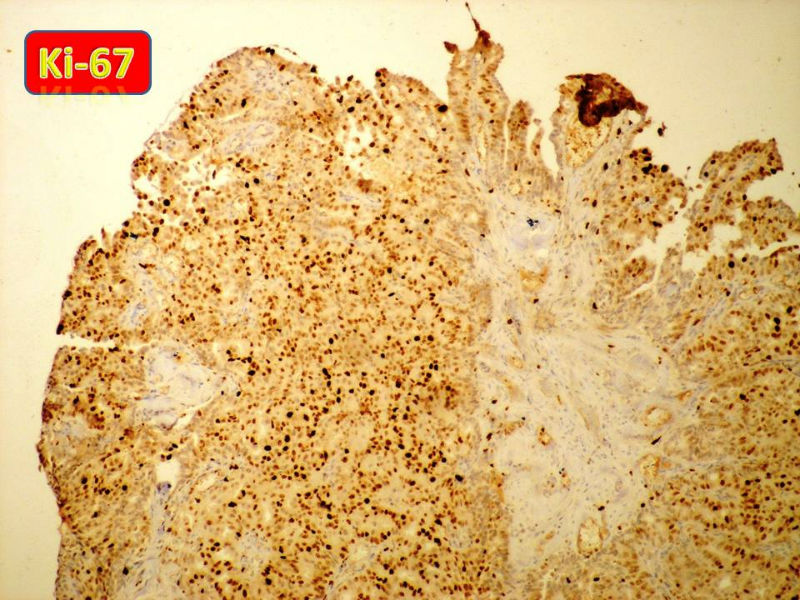

只能说是乳头状瘤

是不是导管内

乳头状瘤 and 导管内乳头状瘤 are the same; Benign lesion.

After you work up and you still cannot be sure it is benign , atypical or maignant lesion, you can call 乳头状lesion.

If this is excisonal case, you should figure out the nature of the papillary lesion.

我的意思就是提醒大家 在不是很确定的情况下 尽量少给自己套枷锁